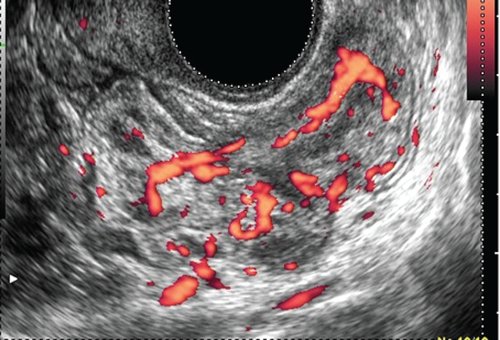

К задней стенке культи шейки матки прилежит участок прямой кишки толщиной до 2,9 см на протяжении до 7,4 см. Стенка кишки неравномерно утолщена до 0,5-0,6 см, пониженной эхогенности, дифференцировать слои стенки не представляется возможным. При ультразвуковой ангиографии на измененном участке определяется выраженная васкуляризация с наличием сосудов с артериальным типом спектра (Vmax 14,4 см/с, RI 0,74). Перистальтика кишечника в данном сегменте отсутствует, внутренний просвет не дифференцируется. Слева от описываемого участка кишечника в межкишечном пространстве определяется гипоэхогенное образование с четкими ровными контурами, неоднородной структуры, размером 2,6х1,9х2,3 см. При ультразвуковой ангиографии в нем лоцируются множественные деформированные сосуды (рис. 1, а, б, в).

а) В-режим.

б) Режим энергетического картирования.

При ультразвуковой ангиографии в стенке определяется выраженная васкуляризация с наличием сосудов с артериальным типом спектра (Vmax 14,4 см/с, RI 0,74).